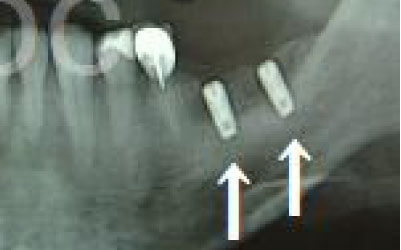

骨が薄い場合、そのままインプラントを行うのはお勧めできません。

ただし、事前に骨を増やす治療を行ったり、インプラントと同時に骨を増やす治療を施したりすることで、インプラントは可能です。

1)インプラント治療を行う前に、骨の治療が必要かもしれません。

2)骨の治療から始めると、その分、治療期間が長くなります。

3)骨の治療は、通常のインプラント治療よりも難易度が高いため、経験の豊富な先生やインプラント認定医のいる歯科医院で治療を受けることをお勧めします。

4)骨の状況をしっかり把握するためにも、CT撮影が必須となります。